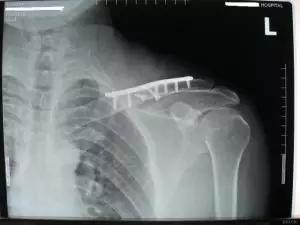

图1:标准的锁骨骨折,此类骨折无需复位。